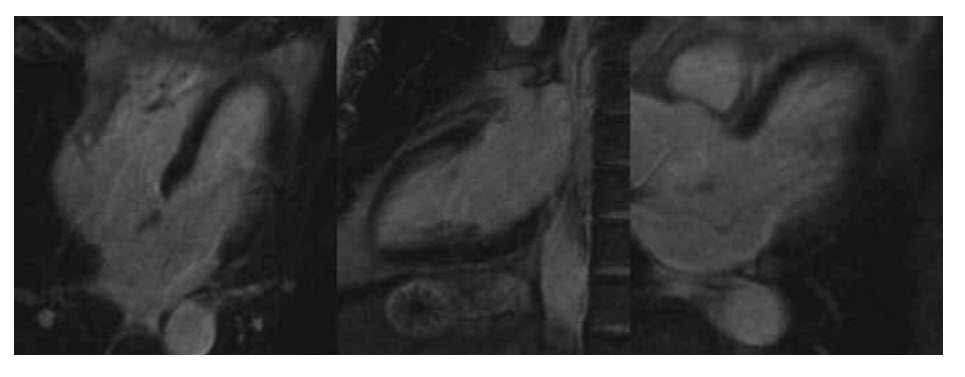

The late myocardial enhancement images are shown ibelow (top row, left to right: basal, mid, and apical short axis; bottom row, four-chamber view).

Which of the following statements is correct?

A. There is right ventricular infarction

B. The Cx territory is viable

C. The LAD territory is infarcted

D. There is a significant pericardial effusion present

E. The RCA territory is non-viable